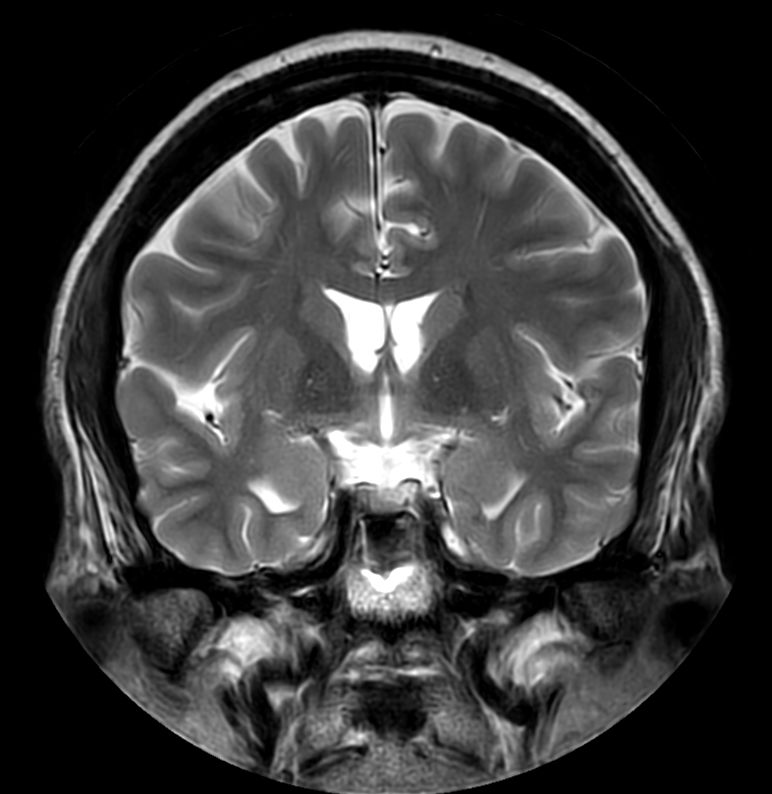

3D T2w FLAIR Compressed SENSE

-

3D T2w FLAIR (Reformat) Compressed SENSE